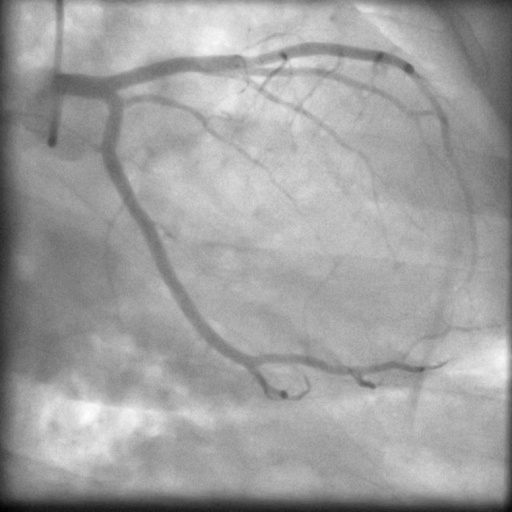

| Image | Ground truth | Video frame | Ground truth | Video frame | Ground truth |

| XCAD [33] | CADICA [19] | Our XACV dataset | |||

4.1 XACV Dataset

We collect 111 complete records of coronary artery X-ray videos, encompassing the injection, flow through the blood vessels around the heart, and dissipation of the contrast agent. Subsequently, we establish the XACV (X-ray Angiography Coronary Video) dataset. Each video consists of varying numbers of high-resolution coronary artery X-ray images. We invite experienced radiologists to annotate the vascular regions, focusing on one or two frames where the contrast agent is most prominent in each video. The XCAD dataset contains only a single image, and the CADICA video dataset does not provide corresponding ground truth. Therefore, in the following experiments, we conduct all the analyses on our collected XACV dataset and the corresponding GT for each sequence. In Figure 5, we show that compared to other publicly available datasets, XCAD [33] and CADICA [19], our dataset exhibits finer annotations in the vascular regions, providing an advantage for future related tasks. The development and use of our dataset have been approved by our institution’s IRB.